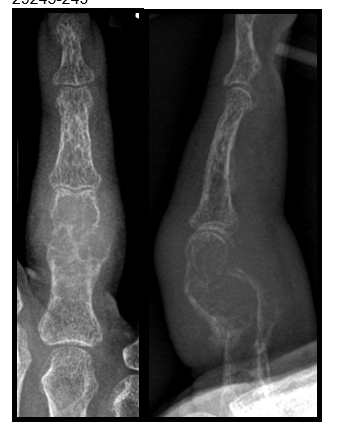

Unklarer osteolytischer Tumor am Ringfingergrundglied

Methoden: Anamnese: 73-jährige Patientin stellte sich 5 Wochen nach einem Schlag ihres Enkels beim Spielen auf die rechte Hand mit seither bestehenden Schmerzen und Schwellung am rechten Ringfinger vor.

Befund: Schwellung des rechten Ringfingergrundgliedes ohne Rötung oder Überwärmung. Fingerbeweglichkeit schmerzhaft eingeschränkt, Faustschluss und Fingerstreckung inkomplett. Schmerzhafte Krepitation im Ringfingergrundglied.

Ergebnisse: Brauner Tumor – Osteitis fibrosa cystica.

Die Osteitis fibrosa cystica, auch brauner Tumor genannt, entsteht im Knochen aufgrund eines primären oder sekundären Hyperparathyreoidismus. Eine pathologisch erhöhte Parathormonsekretion stimuliert die Osteoklastenaktivität und führt zur Bildung von Hohlräumen im Knochen. Es kommt zu Einblutungen (Hämosiderinablagerungen → braun → brauner Tumor), die den osteoklastären Knochenabbau weiter fördern, so dass sich schließlich größere auch radiologisch nachweisbare Osteolysen bilden.

Der Erkrankungsgipfel liegt über dem 40. Lebensjahr. Das Auftreten insgesamt wird als selten beschrieben wobei Zahlen zur Inzidenz fehlen. Der braune Tumor kann in allen Knochen in Erscheinung treten, häufig jedoch an den Phalangen.

Abbildung 1 [Fig. 1]